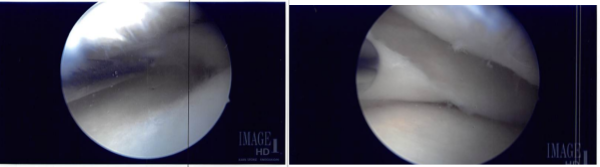

The knee was lavage with a lot of fluid to clean up the blood. visualization was not proper to the blood. The scope was moved to the medial tibiofemoral compartment. The medial meniscus was intact. There was no chondral damage. The scope was moved to the intercondylar area where partial ACL tear of the lateral side was found.

The debridement was done. The rest of the 90% of ACL was intact. The scope was moved to the lateral tibiofemoral compartment where the tear of the medial edge of the lateral meniscus was present. The tear was cleaned using right-sided biters and shavers. The rest of the lateral meniscus was intact. There was no chondral damage.

The scope was moved to the patellofemoral joint where trochlea grade 2 to grade 3 chondral damage was found. The chondral damage was debrided from the medial portal and followed by the lateral portal.

Copious lavage was performed. Arthroscopic pictures were taken and saved. The scope was removed. The knee was extended. The table was extended and a proper draping was performed. A midline vertical incision was put and centered over the superior pole of the patella.